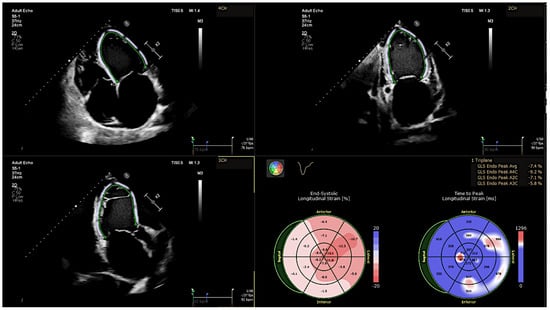

2.2.2. Speckle-Tracking Echocardiography

| GLS, % | −7.1 ± 2.1 | −10.3 ± 2.5 | <0.001 |

| GCS, % | −11.1 ± 3.4 | −16.9 ± 4.2 | <0.001 |

| GRS, % | 15.5 ± 7.8 | 25.7 ± 7.8 | <0.001 |

| LVEF, % | 22.1 ± 6.0 | 33.6 ± 7.3 | <0.001 |